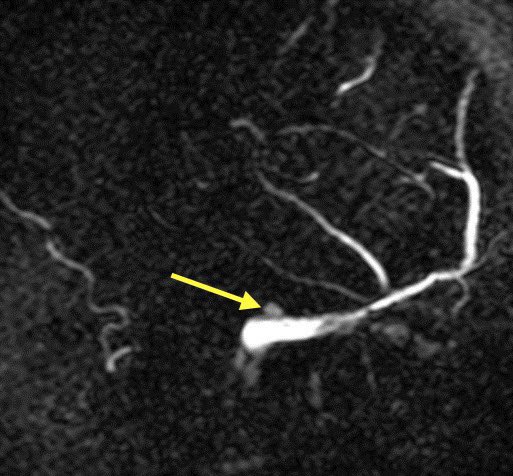

🔹Condylar veins are anastomotic emissary veins that connect the distal sigmoid sinuses or proximal jugular veins with the suboccipital and deep cervical venous plexus

🔹These are often observed incidentally though have been associated with PT